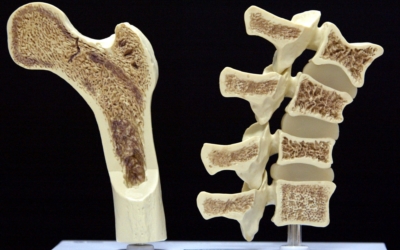

골다공증이란

골다공증이란 단단해야 할 뼈가 약해져서 부러지기 쉬운 상태가 되는 질환을 말해요. 골다공증이란 이름 그대로 약해진 뼈에 구멍이 송송 관찰되는 모습 때문에 지어진 명칭입니다. 나이가 들어가면서 관절이 약해지고 골다공증 으로 고생하게 돼요. 골다공증은 노화때문에만 발생되는 것이 아니랍니다.

작은 쇼크을 받아도 다치기 어렵지 않고 골절이 쉽게 오는 골다공증 증상은 과한 다이어트, 음주, 흡연, 규칙적이지 않은 식생활로 젊은분들에게도 골다공증이 많이 나타나고 있습니다. 여성의 경우, 폐경 후에 여성호르몬 분비가 다운되어 골밀도가 저하되므로 뼈가 스펀지처럼 되어 골절이 쉽게 오는 것으로 보입니다. 대퇴골, 손목 척추, 발목 부위에서 주로 골절이 발생하기 때문에 평소 골다공증에 좋은 음식 또는 스트레칭, 수영, 가벼운 산책 과 같은 저강도 운동을 하시는 게 좋겠네요.